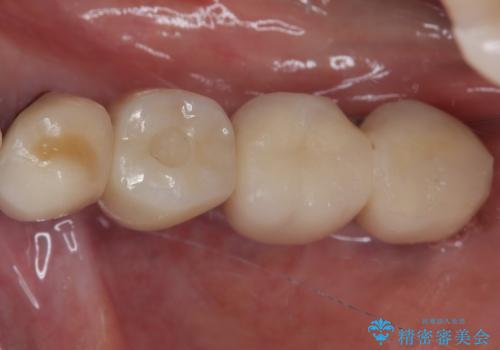

インプラント埋入時に植立具合の安定性を測定したところ、十分な数値が得られたため、速やかに仮歯を装着して咬合回復をさせることができました。

抜歯を含めた外科処置を1回に抑えることができ、あっという間に治療を終えることができました。